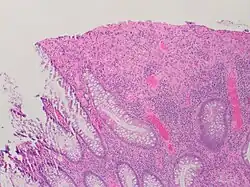

A micrograph demonstrating cryptitis, a microscopic correlate of colitis. H&E stain.